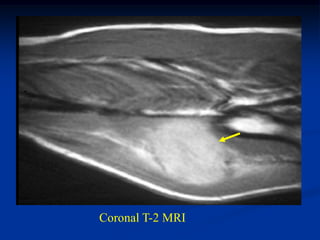

Case #261

62 year female

MFH anterior thigh

AP x-ray

Sagittal T-2 MRI

Axial T-2 MRI

Case #261 62 yearfemale MFH anterior thigh AP x-ray